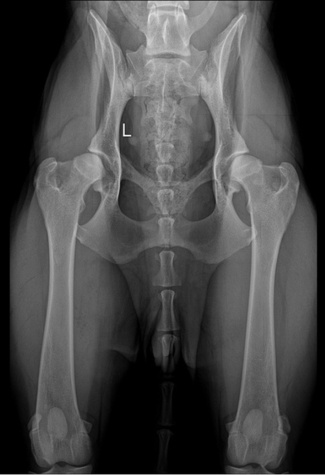

Hip dysplasia (HD) is the most common hereditary disorder of skeletal development in dogs and it is non-congenital. It commonly leads to the detrition of the articular cartilage, synovitis, and secondary osteoarthritis.

HD is usually not detectable in puppies younger than 3 months. A definite and official diagnose of HD by the Finnish Kennel Club Radiologist is only possible after the age of 12 months. In giant breeds this is only possible after the age of 18 to 24 months, depending on the breed. In Finland HD is graded from A to E using ventrodorsal extension radiographs as standardized by Fédération Cynologique Internationale (FCI).